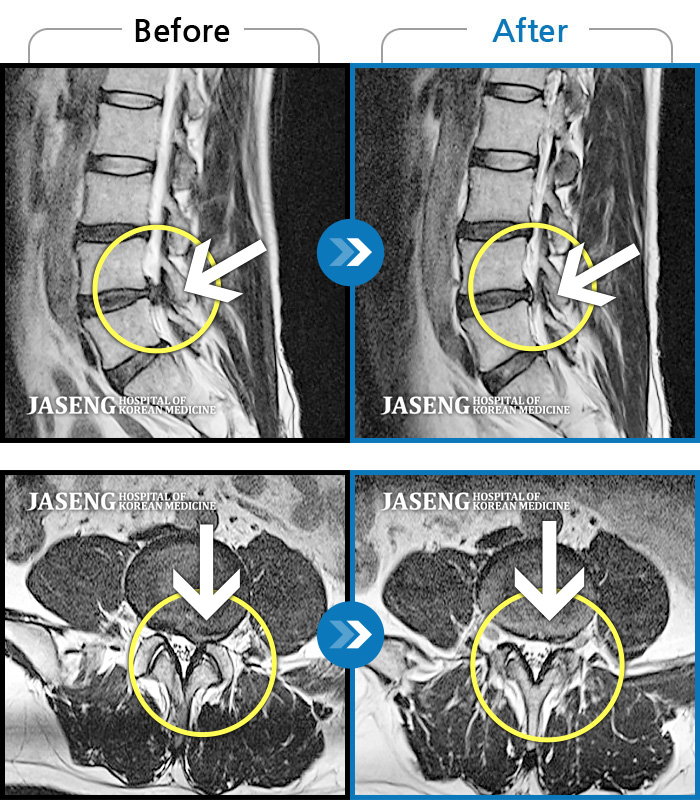

Before

After

환자에게 사전 동의를 받아 동일 조건에서 촬영되었습니다.

개인에 따라 치료 후 부작용이 발생할 수 있으니 의료진과 상담 후 치료를 진행하시기 바랍니다.

기침하면 허리 통증 발생, 몸을 비틀면 우측 허벅지에서 종아리까지 통증

서서 움직일 때, 앉았다 일어날 때 허리 및 우측 다리 통증